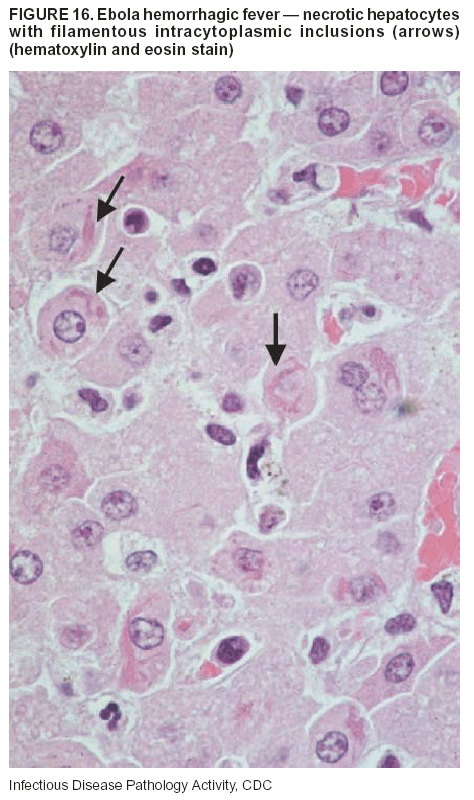

Pathologic Findings. The term viral hemorrhagic fever is reserved for febrile illnesses associated with abnormal vascular regulation and vascular damage. Common pathologic findings at autopsy include petechial hemorrhages and ecchymoses of skin (Figure 15), mucous membranes, and internal organs. Although systemic hemorrhages occur in the majority of viral hemorrhagic fevers, certain agents infect specific cells and thus histopathologic features can differ among agents. Necrosis of liver and lymphoid tissues, as well as diffuse alveolar damage, occur in the majority of viral hemorrhagic fevers, but can be more prominent for certain infections (e.g., midzonal hepatocellular necrosis is prominent in yellow fever, but not in dengue). Viral inclusions can be visualized in hepatocytes with Ebola or Marburg infections by using light and electron microscopy (Figure 16) (49--54).

Diagnostic Specimens. Performing a complete autopsy with histologic sampling of multiple organs can determine the extent of the disease and help identify the specific virus. After a specific etiologic agent has been isolated or identified from an index case, targeted sampling of additional cases with similar symptoms can decrease the exposure of autopsy personnel to these hazardous agents and still yield diagnostic material. For example, during outbreaks of Ebola hemorrhagic fever in Africa, using IHC on skin punch biopsy samples was sufficient to provide a diagnosis in a substantial number of fatalities and minimized the risk to the medical personnel who obtained the specimens (49).

Diagnostic Tests. Serum and skin samples can be tested by using PCR, immunohistochemistry, and electron microscopy (Figure 17). Additionally, serum can be inoculated into experimental animals or culture cells for viral isolation.